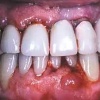

Pildid

Parodontiit